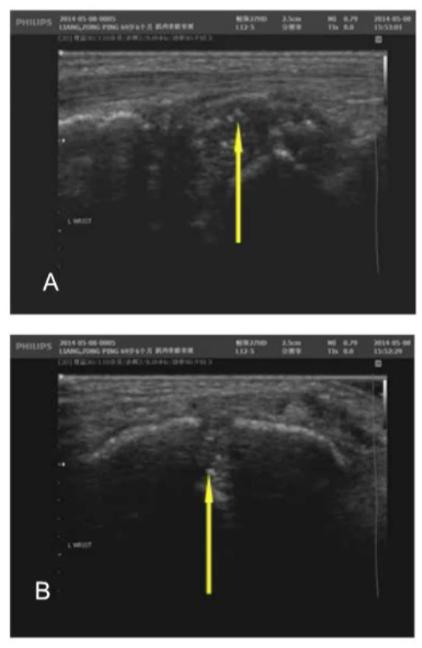

图5:患者MRI表现,无骨端骨质舒松,与常见的类风湿关节炎不同患者的影像学表现均与以往类风湿关节炎的常见表现不同,又对患者进行了超声检查。

图6:腕关节内可见点状高回声

图7:掌指关节软骨表面可见线状高回声,提示“双轨征”苏茵主任指出,在关节超声表现下出现“双轨征”提示“尿酸盐的结晶”。